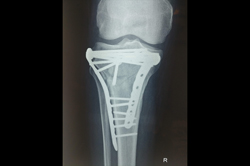

Osteoarthritis – High Tibial Osteotomy - HTO